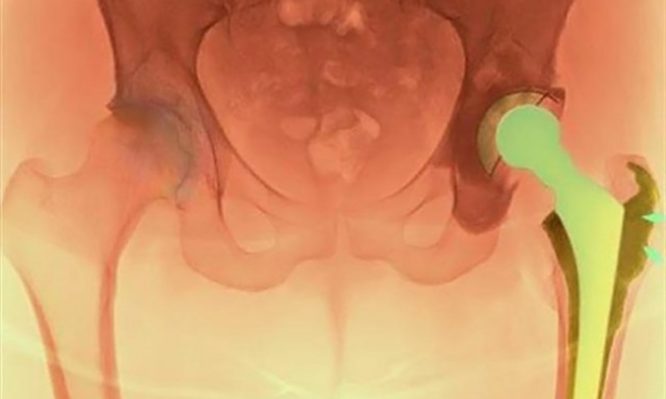

Η ολική αρθροπλαστική ισχίου είναι μία από τις πιο επιτυχημένες χειρουργικές επεμβάσεις στην ορθοπαιδική. Ωστόσο, ένας σημαντικός αριθμός ασθενών υποβάλλεται σε αναθεώρησή της (δεύτερη επέμβαση/επανεπέμβαση) λόγω μηχανικών προβλημάτων (χαλάρωση ή φθορά της πρόθεσης, κακή τοποθέτηση), μικροβιακών λοιμώξεων ή κατάγματος κοντά στην πρόθεση. Σε αρκετούς από αυτούς τους ασθενείς η αναθεώρηση μπορεί να μην έχει τα επιθυμητά αποτελέσματα και έτσι θα χρειαστεί να υποβληθούν σε επέμβαση αναθεώρησης για δεύτερη, τρίτη, ακόμα και τέταρτη φορά. Σημειώνεται ότι, οι επεμβάσεις αναθεώρησης στο ισχίο απαιτούν μεγάλες τομές, σοβαρές κακώσεις στα μαλακά μόρια και έντονη απώλεια αίματος, ενώ συνοδεύονται από αυξημένο ποσοστό επιπλοκών σε σχέση με την αρχική επέμβαση.

Η πρωτοποριακή μέθοδος ASI είναι η πιο σύγχρονη μέθοδος ελάχιστης επεμβατικότητας και χρησιμοποιείται με μεγάλη επιτυχία σε περιπτώσεις που είναι αναγκαία η αναθεώρηση της κοτυλιαίας πρόθεσης. Ορισμένα από τα βασικά πλεονεκτήματα της μεθόδου ASI, είναι η ελαχιστοποίηση του κίνδυνου για μετεγχειρητικά εξαρθρήματα, η εξάλειψη του κίνδυνου για μετεγχειρητική ανισοσκελίακαθώς και η πρόσβαση στην παλαιά πρόθεση και η τοποθέτηση και ο προσανατολισμός της νέας με μεγαλύτερη ευκολία και αξιοπιστία. Παράλληλα, μειώνεται ο χρόνος αποκατάστασης και αποφεύγονται οι επιπλοκές που συνοδεύουν τη μακρά περίοδο ανάρρωσης μετά από εκτεταμένες προσπελάσεις του ισχίου, ενώ δεν χρειάζεται μετάγγιση.